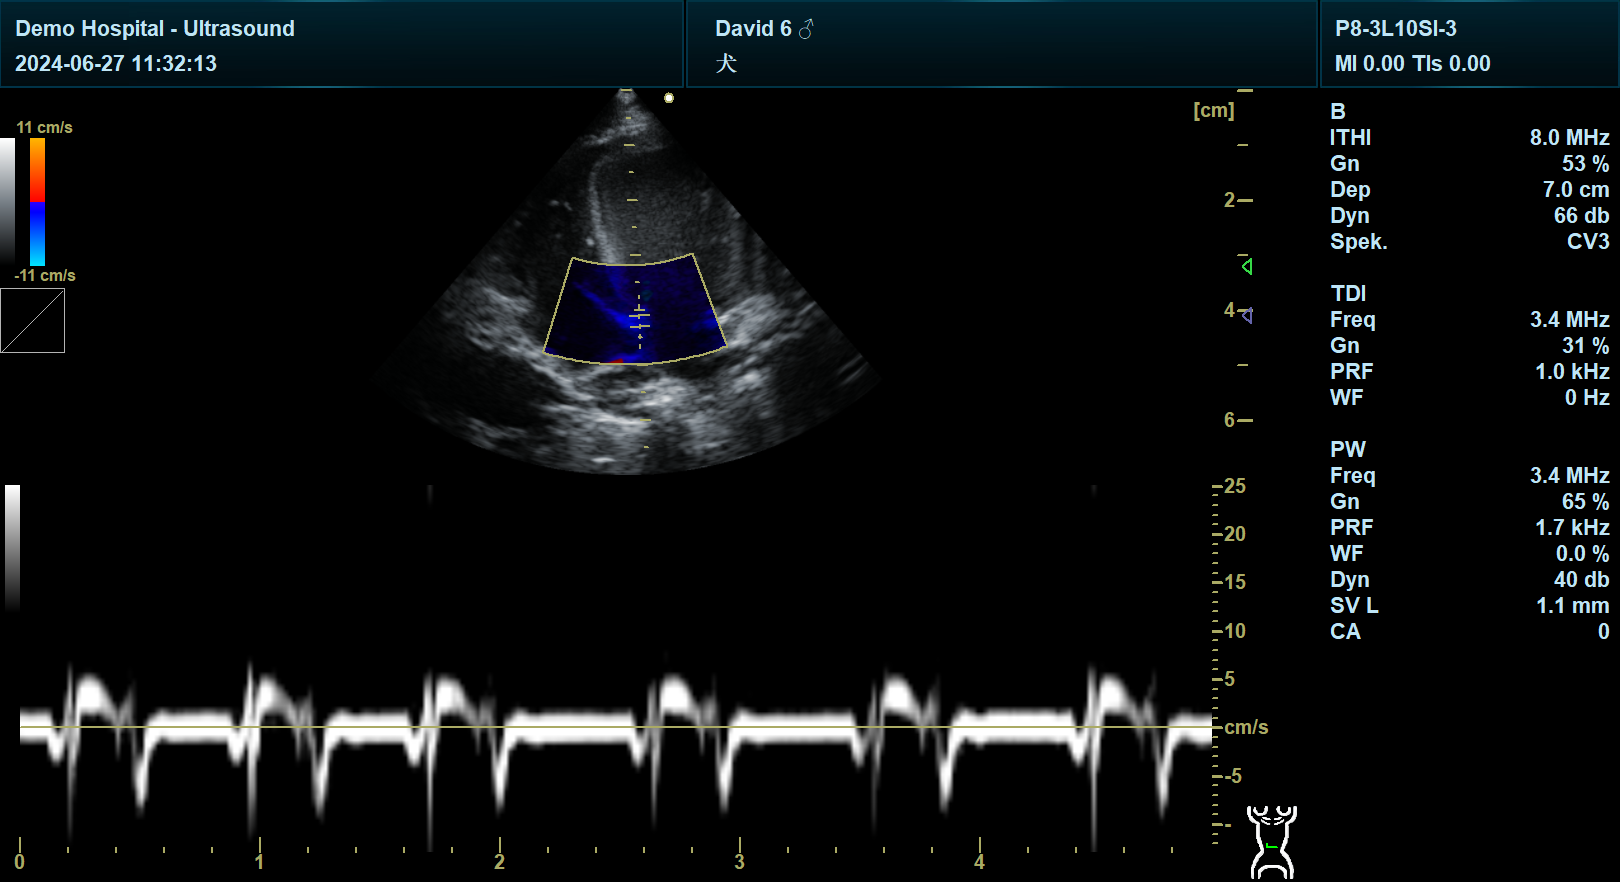

犬左侧胸骨旁长轴右心耳切面的超声扫查,并非标准规范切面,临床中通常需结合左侧胸骨旁长轴面等基础切面,通过调整探头角度和位置来间接观察右心耳区域,具体操作需依据动物个体差异和心脏结构特点灵活调整。

观察结构:右心室、三尖瓣、右心房。

操作意义:通过右侧切面验证右心耳形态,与左侧切面观察结果相互印证,提高诊断准确性。

形态异常:右心耳扩张可能提示三尖瓣反流、右心衰竭或心包积液。

心肌病:右心耳扩张可能伴随扩张型心肌病或限制型心肌病。